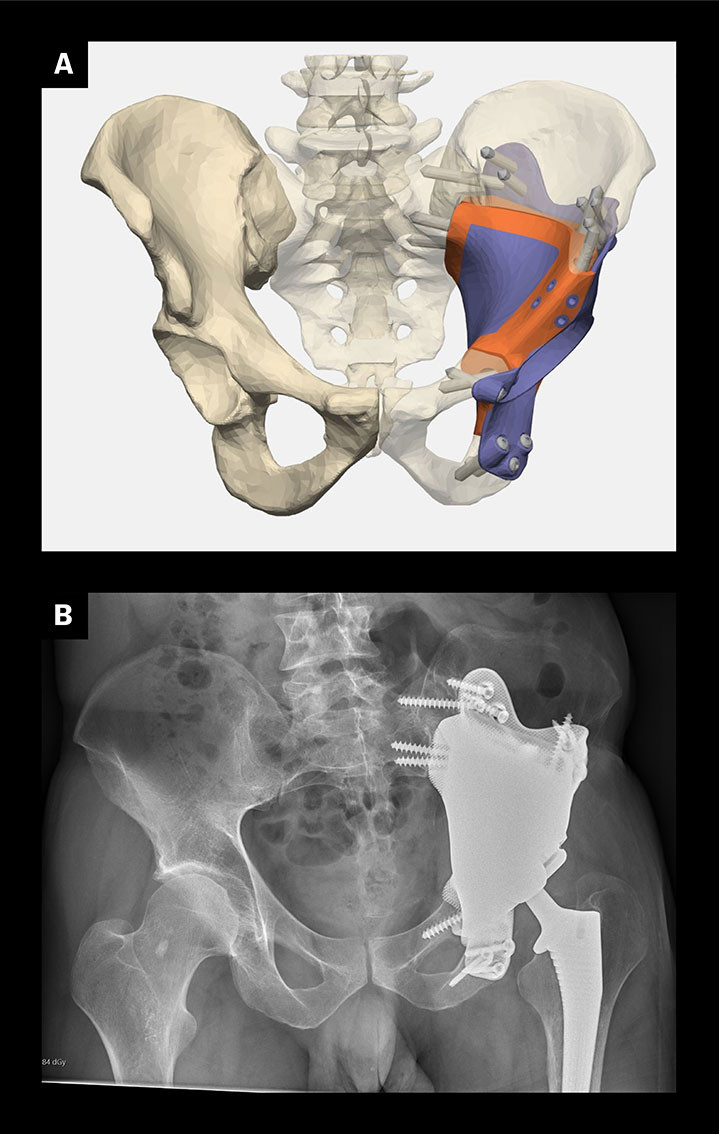

Modern imaging diagnostics can accurately calculate bone defects following cancer surgery, deformities and injuries. Titanium implants can be custom-made to match the patient's anatomy, replacing and perfectly adapting to the bone loss. The implant is produced using 3D printing and is surface treated, then anchored in the remaining bone around the skeletal defect (Figure 3). This can, for example, help recovery of gait function after removal of a pelvic tumour, compensate for cranial defects, restore face shape and improve the masticatory function (20, 21).